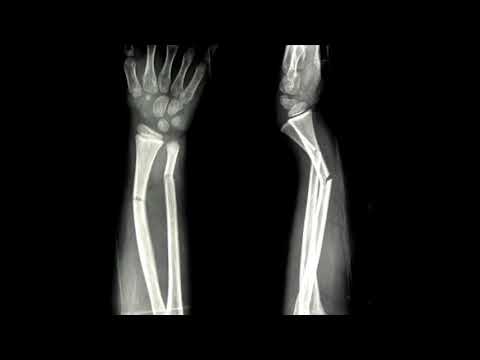

Bone Trauma (RIFE Healing Frequency)